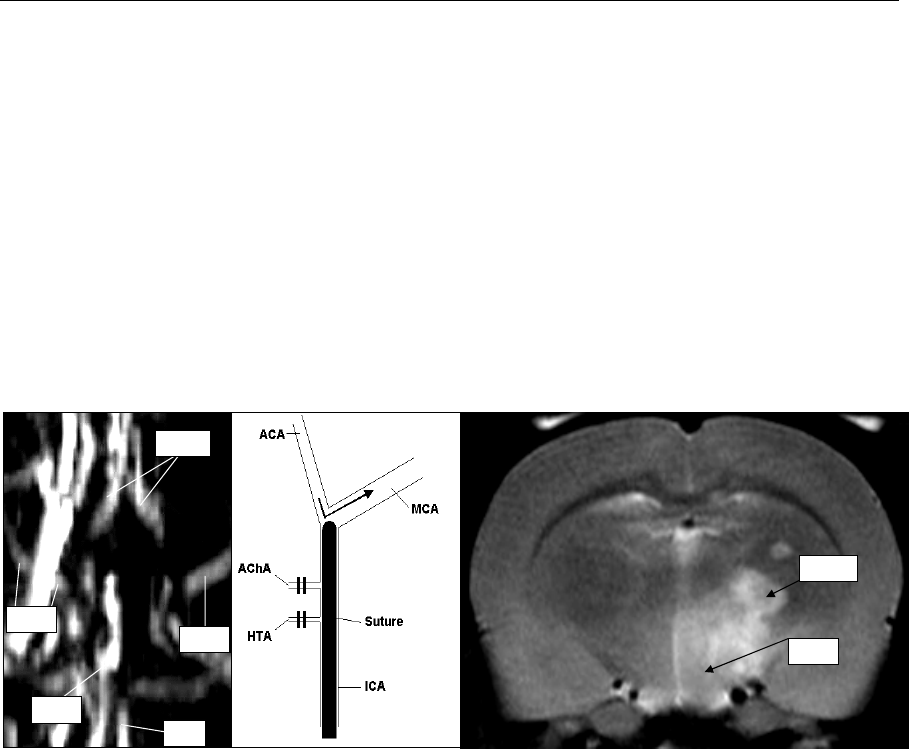

Abb.35: Typische Fehlerquelle des Fadenmodells: Die MR-Angiographie (links) belegt, dass der MCA-

Hauptstamm nicht verschlossen war. Dennoch zeigte dieses Tier fokalneurologische Defizite.

Ursächlich ist ein Infarkt im Versorgungsgebiet der A. choroidea anterior und der A. hypothalamica

(sichtbar auf dem T2-gewichteten MRT rechts). Die Schemazeichnung (Mitte) verdeutlicht die

Fehllage des Okkluders: Der Faden wurde nicht ausreichend weit vorgeschoben und führte zu einem

Verschluss der beiden Äste aus der A. carotis interna, nicht jedoch zu dem angestrebten MCA-

Hauptstammverschluss.

MCA=A. cerebri media; ACA=A. cerebri anterior; ICA= A. carotis interna; BA= A. basilaris; AChA=A.

choroidea anterior; HTA=A. hypothalamica